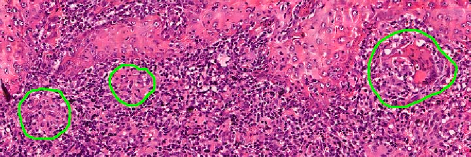

Leishmaniasis background and histology presentation. The World Health Organization (WHO) has selected cutaneous leishmaniasis as a neglected tropical disease (NTD) with growing, uncontrolled, and ignored infection affecting millions of people every year [14, 9]. It is unfortunately one of the world’s most neglected poverty-related diseases, affecting the poorest people in developing countries and it is associated with risk factors like malnutrition, immune system deficiency, migration, inadequate education, illiteracy, gender inequality, and a shortage of services [1]. Furthermore, only eight countries in the world contribute to 90% of leishmaniasis cases: Afghanistan, Algeria, Brazil, Iran, Pakistan, Peru, Saudi Arabia, and Syria [12]. It is a vector-borne infection caused by the protozoan parasite Leishmania. The vector is the female sand-fly. The lesions of cutaneous leishmaniasis vary in presentation ranging from a single self-limited skin lesion to multiple large destructive and ulcerated lesions on mostly the exposed parts of the body such as face, forearms, and lower legs [2]. Skin biopsy is considered the gold standard method for confirmation of diagnosis. The presence of large epitheloid granulomas and small hematoxylinophilic LD bodies (that are round, uniform in appearance, intracytoplasmic and sometimes distributed around the outer rim of the vacuoles) is critical for diagnosis and confirmation of leishmaniasis [4]. Large granulomas are visible at 10X but the smaller hematoxylinophilic bodies (around 3-4mm in size) are usually visible at 40X and can easily be missed if they are few in number, leading to misdiagnosis. Specialized dermatopathologists are the only ones who can diagnose these accurately based on patient history, clinical features, and laboratory diagnosis. It is thus critical to share the digitized slides of these cases from rural poor remote areas with dermatopathologists (mostly residing in urban centers) for quick diagnosis and accurate management of the patient.

We demonstrate our WSI creation workflow on Leishmaniasis cases, as shown in Figures 1 and 4. An expert pathologist reviewed the cases and annotated granulomas as well as LD bodies on the stitched images and our generated images in Figure 4. To show generalizability of our approach, we also show results on core biopsies of breast, duodenum, stomach, liver, and lymph nodes (Figure 5).